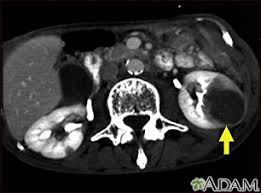

I tell my patients, if you're in your 70s and have an early stage 1 kidney tumor, it's much more likely (up to five times in some studies) that you will die of something other than kidney cancer over the next five years. Kidney cancer recurrence & survival rates. The accumulating abnormal cells form a tumor that can extend beyond the kidney. Kidney tumor with suspicion of spread. Whether the cancer has spread to other areas of the body (metastasised). While the only way to know for sure if you have kidney disease is to get tested, dr. How to tell if your cancer has metastasized. Finding out the stage of the cancer helps doctors to advise on the best treatment options.

If kidney cancer spreads, it can spread to the following: You may have been told that the kidney cancer has spread. In march of 2017 i had a left nephrectomy and the removal of a tumor in the inferior vena cava. My doctors and i have been vigilant about doing 6 month mris and unfortunately, there has been a recurrence of the kidney cancer in lymphnodes on my right side. How do i know if my kidney cancer has spread to other organs? Kidney tumor with suspicion of spread. And within a stage, an earlier letter (or number) means a lower stage. Kidney cancer recurrence & survival rates. Whether the cancer has spread to other areas of the body (metastasised). N is used to identify how far the cancer. It occurs in one of three ways: Vassalotti shares 10 possible signs you may have kidney disease. Early kidney cancer (stages i and ii) is localised.